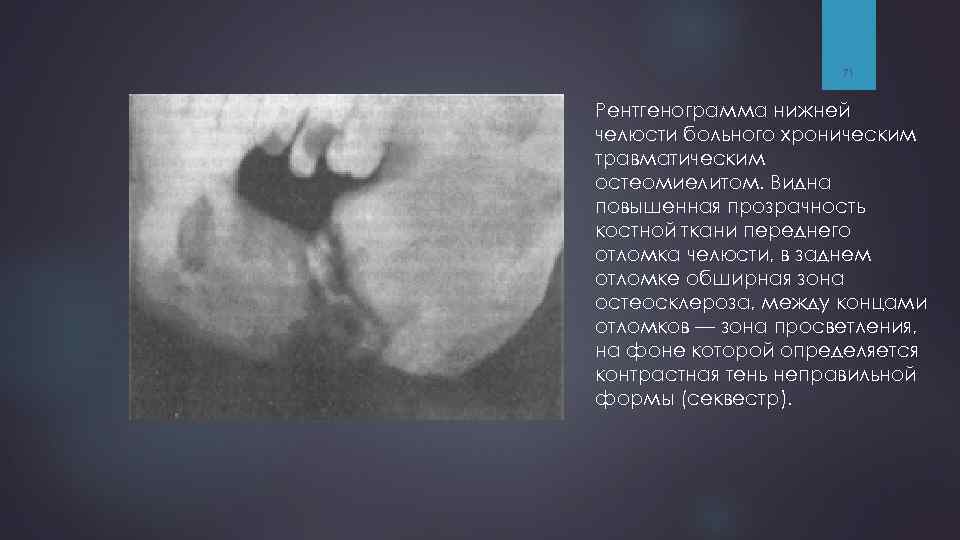

71 Рентгенограмма нижней челюсти больного хроническим травматическим остеомиелитом. Видна повышенная прозрачность костной ткани переднего отломка челюсти, в заднем отломке обширная зона остеосклероза, между концами отломков — зона просветления, на фоне которой определяется контрастная тень неправильной формы (секвестр).